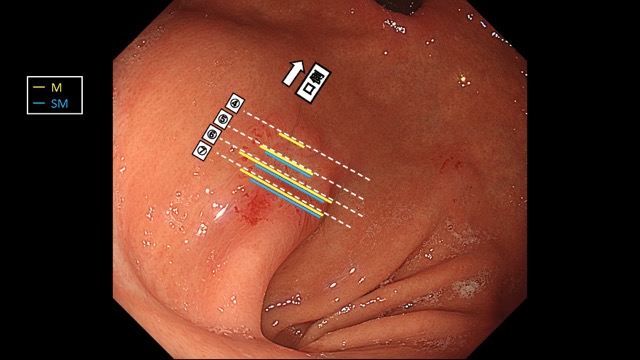

胃012